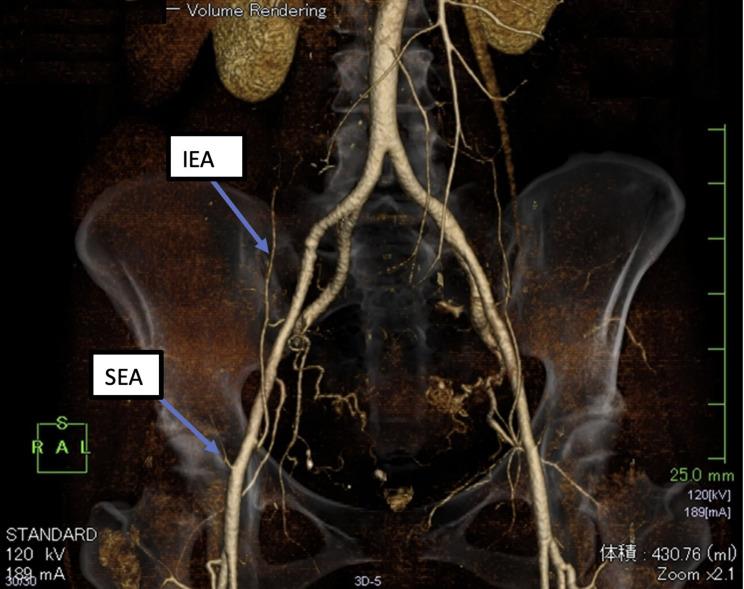

Case presentation: A 40-year-old female underwent bilateral ultrasound-guided rectus sheath block and transversus abdominis block following laparoscopic cholecystectomy. After the operation, a large, painful hematoma was identified with a volume estimated at 430 mL. Investigation of the bleeding site by CT scan showed that the hematoma was subcutaneous and in an area with multiple venous and arterial branches. Identification of the responsible vessel appeared difficult; however, on discussion with the radiologist, bleeding from a cutaneous (or deeper) vessel from the block or surgical (trocar or needle) injury was included in the different diagnosis. The superficial epigastric artery was considered the most probable source because it was the closest to the hematoma.

Conclusion: Although the IEA and IEV are the major candidates for vascular injury in rectus sheath block, clinicians should recognize that the SEA can also be injured during rectus sheath block procedures.